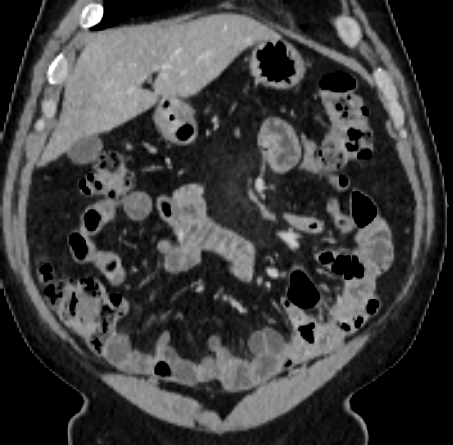

Over the years, there have been attempts to develop automatic methods for small bowel segmentation, especially using deep learning. The small bowel was included in segmenting multiple organs-at-risk for radiotherapy treatment planning of affected tissues, such as pancreatic and cervical cancers, in CT scans [8, 9, 13]. Although the results obtained for the small bowel are reasonable, some of their data included only the part of the small bowel that is closest to the target area, which needed to be dose-evaluated [8, 9]. In [13], the rough bowel location was detected instead of performing pixel-accurate small bowel segmentation. There have been only a few previous works dedicated solely to automatic small bowel segmentation [12, 14, 21]. While the specific anatomic relationship between the mesenteric vasculature and the small bowel is used to guide the small bowel segmentation in [21], a cylindrical shape constraint is applied during training of the small bowel segmenter in [14]. Although each of the works showed reasonable performance for particular datasets, their generalizability across different datasets was not evaluated. A CT scan is acquired using a specific imaging protocol depending on the purpose of the investigation, which includes the use of different contrast media and scan timing. Thus, the appearance of the small bowel may be different across datasets as exemplified in Figure 1. It is observed in our experiment that, when trained on one dataset, the model does not generalize well to another dataset due to the domain shift (section 3).

In this paper, we present a novel unsupervised domain adaptation method for small bowel segmentation, which is based on feature disentanglement. Although the absolute intensity values in CT scans (Hounsfield units) carry important information on specific substances of the human body, thus could provide a clue of being specific tissues and organs, they may be variable according to the imaging protocol. Figure 1 shows example CT scans that were acquired with and without oral contrast administration. The absolute intensity values are no longer a strong clue for the small bowel when we train and test across the datasets. Non-intensity features like texture and shape may be more useful. For example, local textures of the valvulae conniventes, which are circular folds on the inner surface of the small bowel, are more recurrent across the datasets.

A

B

B

C

C

D

D